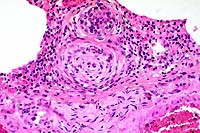

- Case 18-1. Lung. Note intimal and medial hyperplasia

of small arteries which nearly or completely occlude the lumens.

The adjacent interstitium is expanded by lymphocytes, anthracotic

pigment, and cell debris.

- AFIP Diagnosis: Lung: Arteriopathy, plexiform, multifocal,

moderate, with diffuse congestion and multifocal alveolar edema,

Maltese, canine.

- Conference Note: Pulmonary hypertension induces a

spectrum of vascular lesions in the lung, some of which have

characteristic microscopic features with diagnostic significance.

Although vessel changes may involve the entire arterial tree,

the lesions are most prominent in arterioles and small arteries.

The lesions of the pulmonary vasculature in this Maltese puppy

are characterized by multifocal medial hypertrophy of small to

medium-sized arterioles, loss of the internal elastic lamina,

and extensive hyperplasia of the tunica intima that narrows or

occludes vessel lumens. Occasionally, the hyperplastic endothelium

forms tufts of small, glomerulus-like, capillary channels that

span the lumens of dilated arterioles, resembling a network or

web (hence, plexogenic pulmonary arteriopathy). Multifocally,

there is fibrosis of the alveolar interstitium.